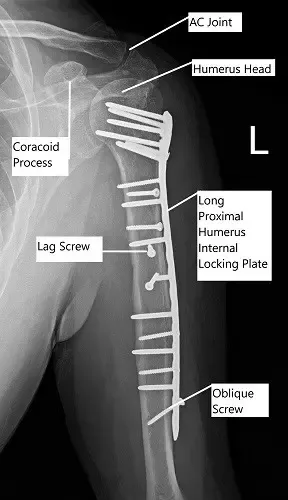

Radiografía postoperatoria del hombro izquierdo en vista AP.

- Reducción abierta y fijación interna de la mayor tuberosidad y eje del húmero utilizando una placa humeral proximal, con 14 orificios, Stryker.

Se formó una placa lateral. Se utilizó una plantilla lateral para determinar que necesitaba una placa de 14 orificios (2,8 mm). Una placa de 14 orificios se oponía lateralmente y luego el cable K avanzaba. La radiografía mostró buena reducción y oposición. La placa se fijaba distalmente mediante tornillos corticales.

Después, la cabeza humeral se fijó usando varios tornillos de bloqueo. La fijación distal en el eje medio y distal se completó con una combinación de tornillos de bloqueo y no bloqueo. Se tomaron y revisaron fotografías que resultaron satisfactorias.